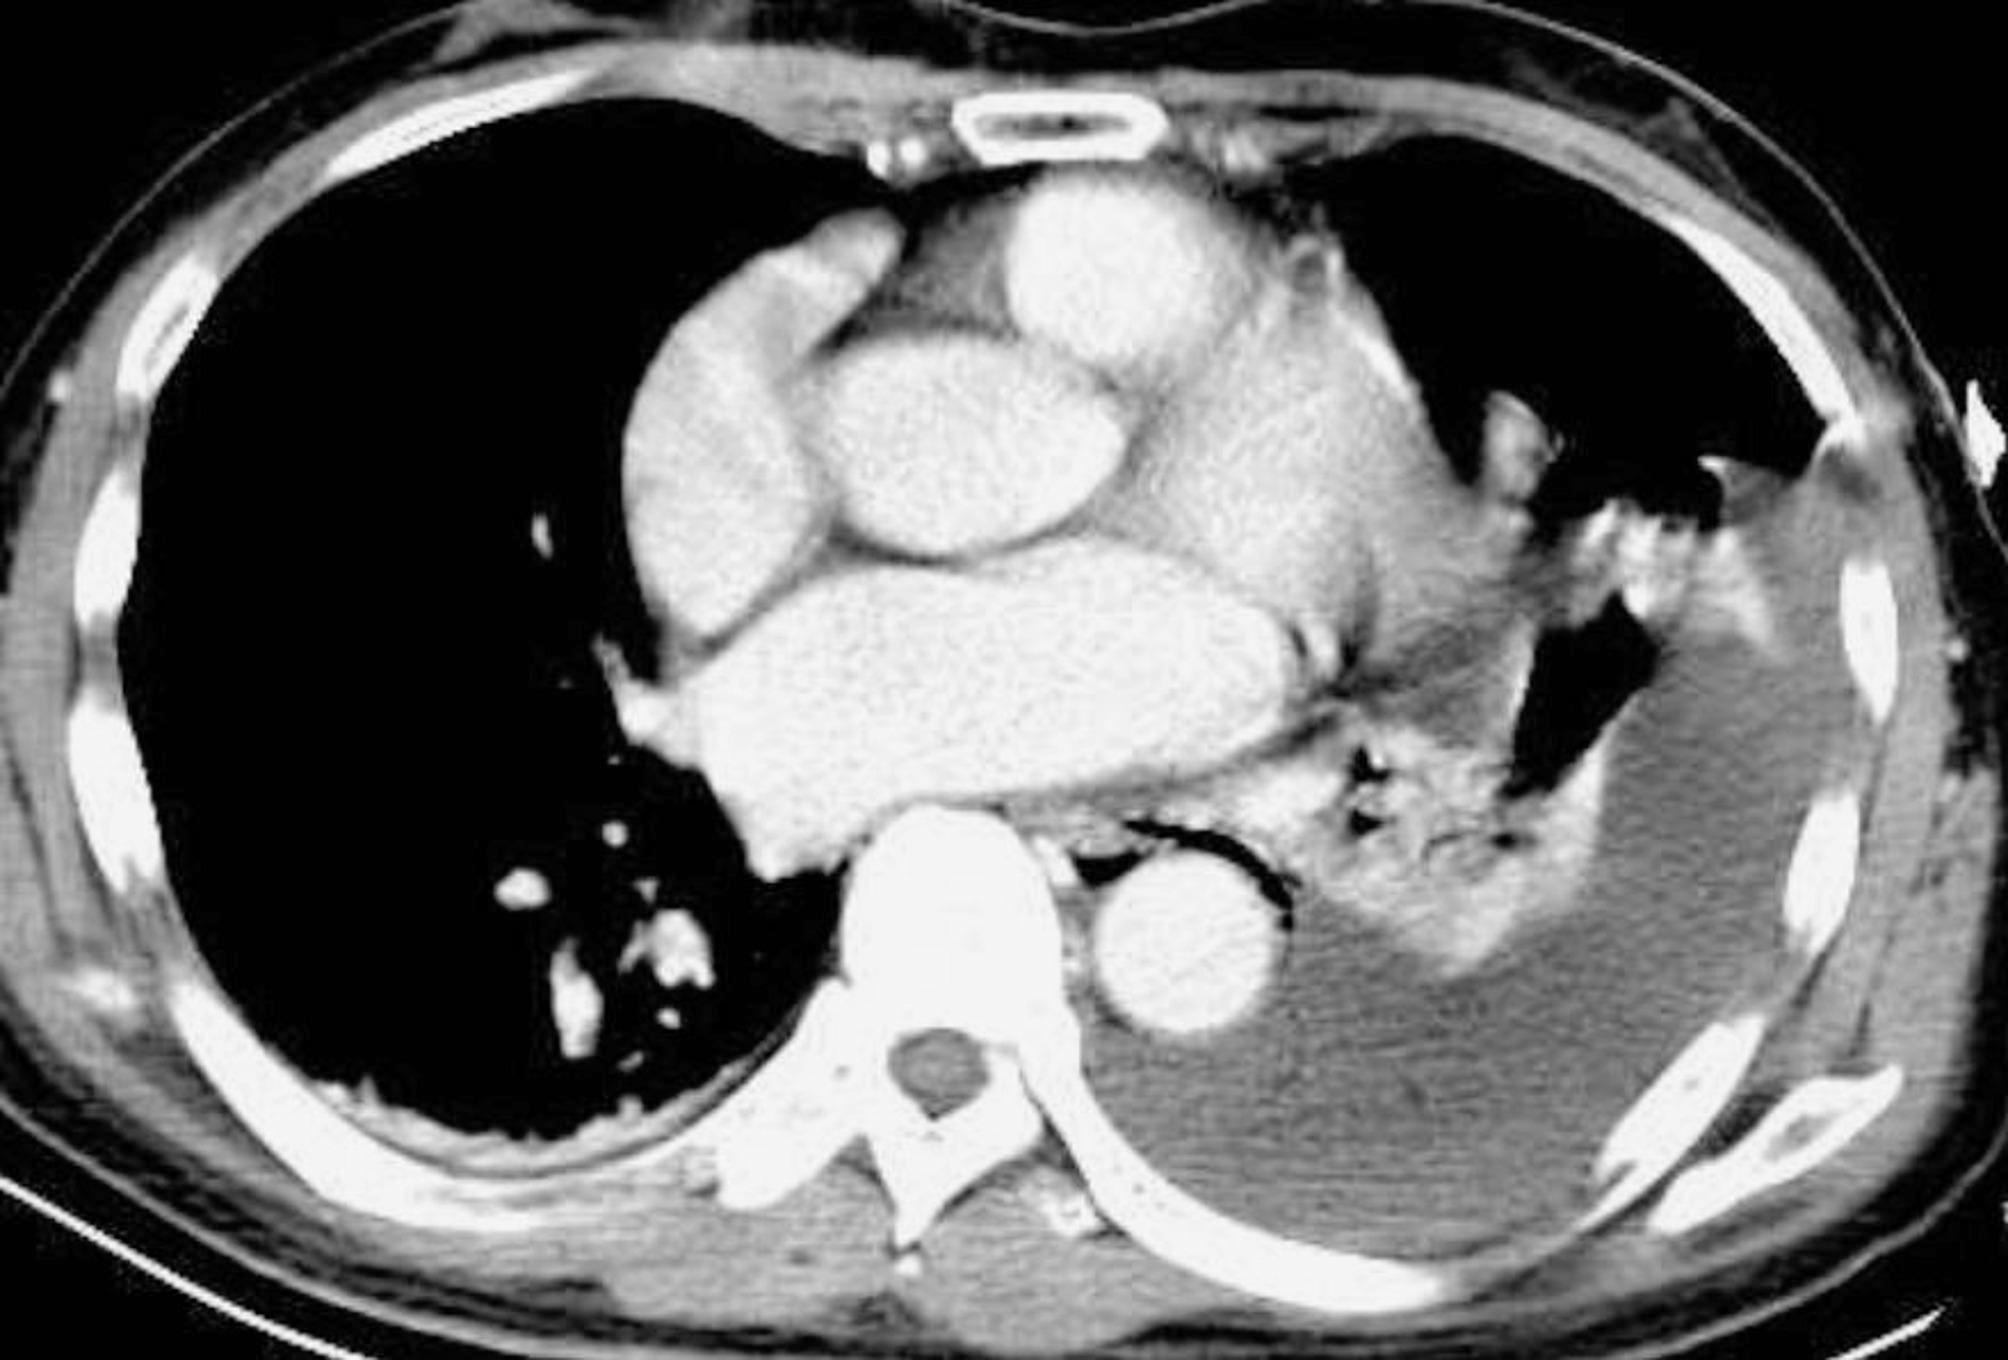

Case presentation: The 65-year-old male patient who was admitted to the emergency department with left chest pain and dyspnoea after severe vomiting. Chest computed tomography (CT) indicated left hydropneumothorax and mediastinal emphysema. The patient underwent bedside closed thoracic drainage. The drainage fluid was coffee-coloured and turbid, with significantly elevated CA199, CA125 and CEA levels. After transferring the patient to the emergency operating room, the esophageal defect was repaired, and a jejunostomy was performed. No tumours were detected in the thoracic cavity during surgery. The patient recovered and was discharged from the hospital.

Conclusion: Esophageal tumours should be suspected in patients with elevated pleural effusion CA199, CA125 and CEA levels. The findings from chest CT and oesophagography did not support the diagnosis of a thoracic tumor.These tumor markers may be concomitant changes during esophageal rupture.